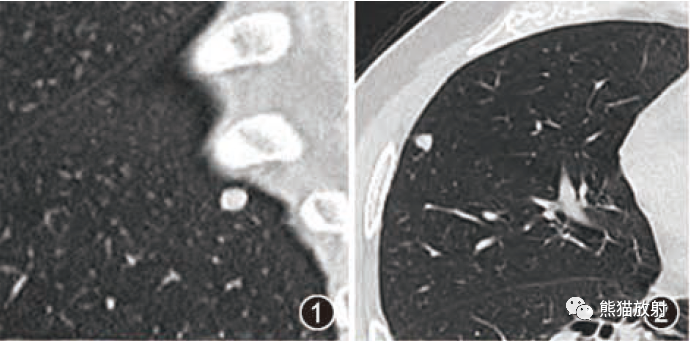

1、腹部平片表现肾影正常或稍增大,两侧或单侧肾实质内多发圆形、类圆形或不规则形结石,直径2-5MM,呈簇状或扇形分布,有时平片可表现阴性。

3、CT平扫表现一个或多个肾锥体内散在或蔟团状多发结石,呈花瓣样或扇形分布;部分腹部平片阴性,CT平扫可发现肾锥体内细小的结石。增强扫描表现扩张的肾集合管内有条纹状、刷状、小囊状或扇形的造影剂浓聚。部分患者肾实质内可见多发小囊肿。